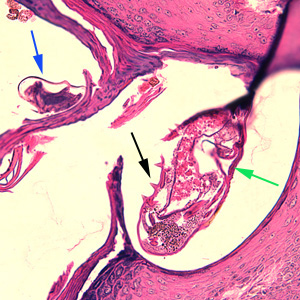

Case #244 – January, 2009

An 80-year-old resident of a long-term care facility presented with a skin condition manifesting as thick crusts over the skin accompanied by slight itching. The patient was originally treated for impetigo, with no resolution, and was ultimately admitted to the hospital for further testing. A skin biopsy was performed. The specimen was sectioned, stained with hematoxylin and eosin (H&E) and sent to a dermatopathologist for diagnostic assistance. Figures A–D show what was observed in the stained sections. Figures A and B were taken at 200x magnification. Figures C and D represent the same fields, respectively, taken at 400x magnification. What is your diagnosis? Based on what criteria?

Figure C